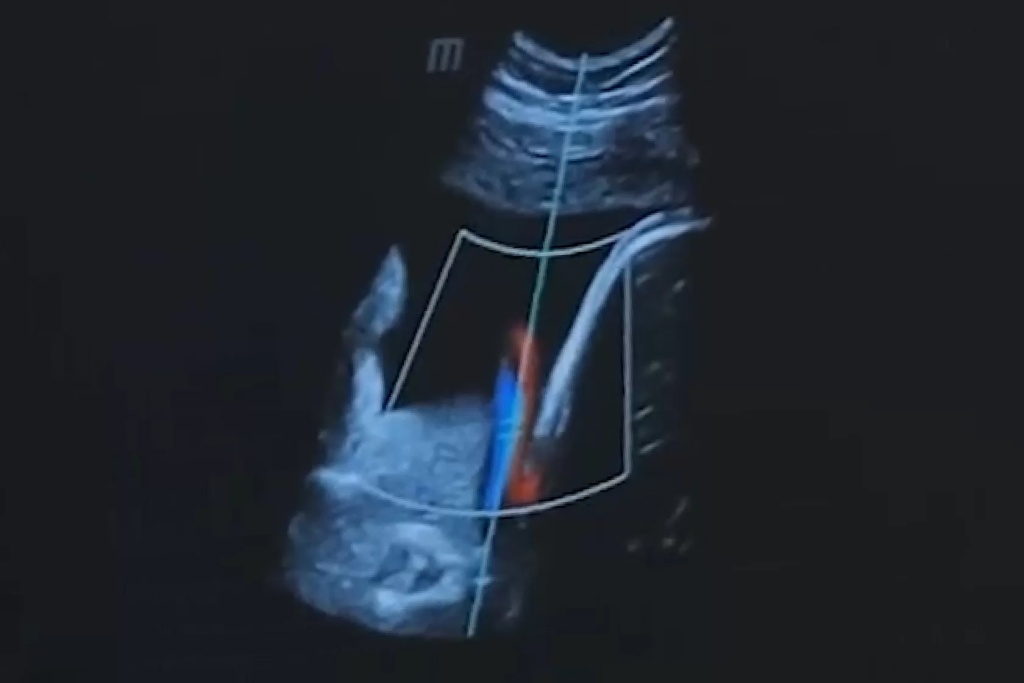

В кардиологии режим тканевой гармоники активно используется для более точной оценки функции сердца и выявления структурных изменений в миокарде. Это содействует более эффективной диагностике и планированию лечения сердечно-сосудистых заболеваний.

Примером успешного применения тканевой гармоники является диагностика опухолей. Этот режим позволяет более четко выделить границы опухоли и оценить ее структуру, что существенно упрощает планирование хирургического вмешательства.

В случае кардиологии, тканевая гармоника позволяет детально изучать состояние сердечной мышцы, обеспечивая более точную оценку функциональных изменений. Это имеет важное значение при выборе оптимального лечения сердечно-сосудистых заболеваний.